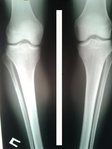

Исходник отличный, внутренний контур голеней чётко выражен.

Дата операции 09.02.2016г.